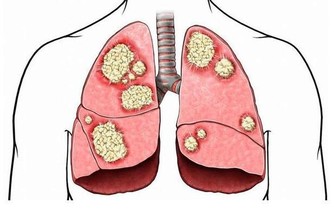

除此之外,冠心病等心血管疾病、各種慢性疾病都會在這個時期爆發,

因此很多人認為這段時間也是“疾病高發期”。

殊不知一些慢性疾病的症狀和更年期症狀比較相似,隱蔽性比較大,